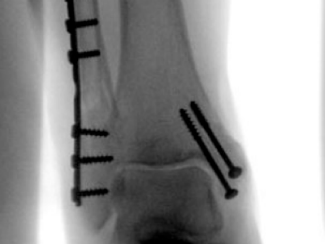

Screws and plates are used to hold bone fragments together. Plates are attached to the surface of the bone with screws to maintain alignment.

These are metal rods inserted into the medullary canal of long bones, such as the femur or tibia. They provide stability along the length of the bone.

Intramedullary Fixation

This involves using an intramedullary nail or rod inserted into the marrow cavity of the bone. It is often used for long bone fractures.